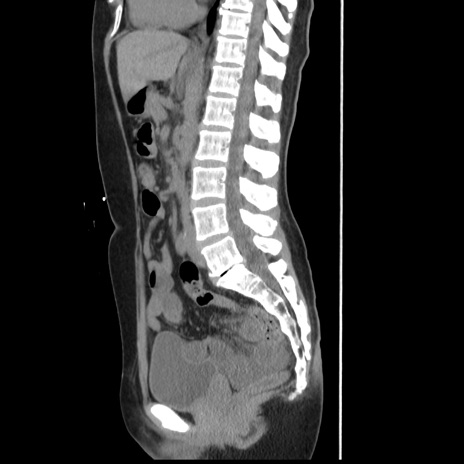

症例10(矢状断像)

【症例】 50歳代女性

【主訴】 腹痛

【現病歴】前日生レバーを食べた。今朝に排便あり。 昼前に突然発症の腹痛を生じ、当院救急外来を受診した。

【既往歴】 子宮筋腫にてで子宮全摘後

【身体所見】 意識清明、腹部:平坦、軟、下腹部やや左を中心に圧痛・反跳痛あり、筋性防御あり

【データ】WBC 7800、CRP 0.07